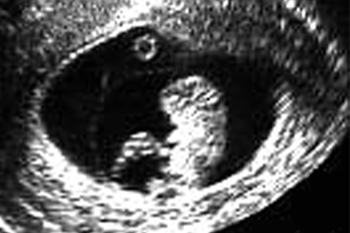

妊娠10週

子宮の中にいる赤ちゃんの超音波写真を見てみましょう。

妊娠中の子宮は、丸くて柔らかく赤ちゃんが心地よく過ごせる場所です。赤ちゃんは本来胎内を、膝を曲げ、指をなめられる姿勢で過ごします。

ところが、子宮まわりの筋肉がコリ固まってカチカチだったり内臓が下がって子宮が押しつぶされたりすると、子宮が細長い形になってしまいます。この中の赤ちゃんは窮屈で楽な姿勢をとることができません。

子宮を横方向に撮影 9週0日